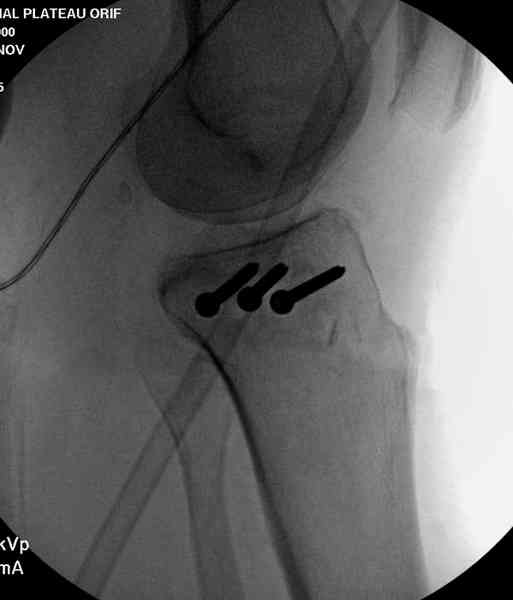

Медиально, обычно на протовоположной

строне, делается окно в кортикальном слое, кривым забойником под рентгеном поднимается импрессия.

Лет 10 назад пытались комбинировать внутрисуставной контроль артроскопом,

но из-за увеличения операционного

времени и сложности манипуляции многие отказались от такой техники.

После заполнения образовавшейся полости в метафизе

кортикальное окно можно прикрыть.